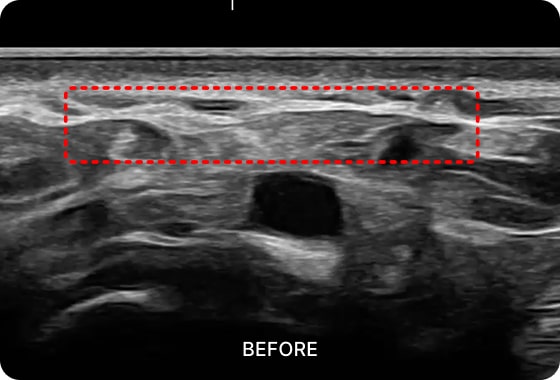

초음파 검사를 통해

수부건초염 통증의 직접적인

원인을 확인할 수 있습니다.

손목에 존재하는 1~6 구획의 건초 상태를

진단하고 정확한 부위를 치료하여 손목과

손가락 통증을 해결합니다.